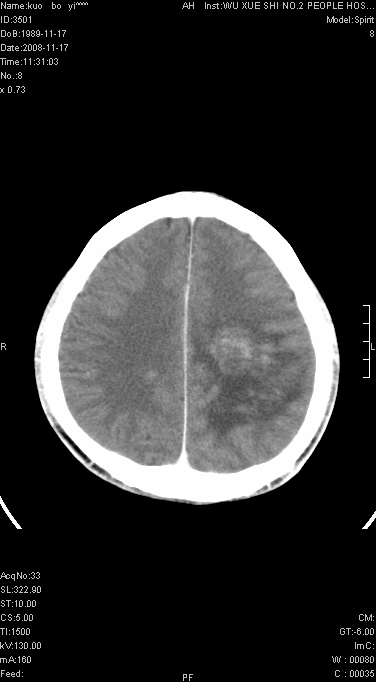

增强后水肿中心高密度灶有明显强化,强化不均匀,呈雪花状或絮状,且强化明显,若为肿瘤,应该出现形态较规则的瘤体影,强也有例外如胶质瘤就可以形态不规则.但胶质瘤明显强化者多为恶性间变性,与病史及相关表现太不相符.因此本例多考虑为炎症引起.

患者年龄才19岁,病史很短,也较符合炎症等短程病变.

左顶叶大范围水肿,内见明显强化的片状 棉絮状组织,但占位效应不明显。考虑脑炎可能性大。

在北京天坛医院治疗考虑寄生虫感.明显好转